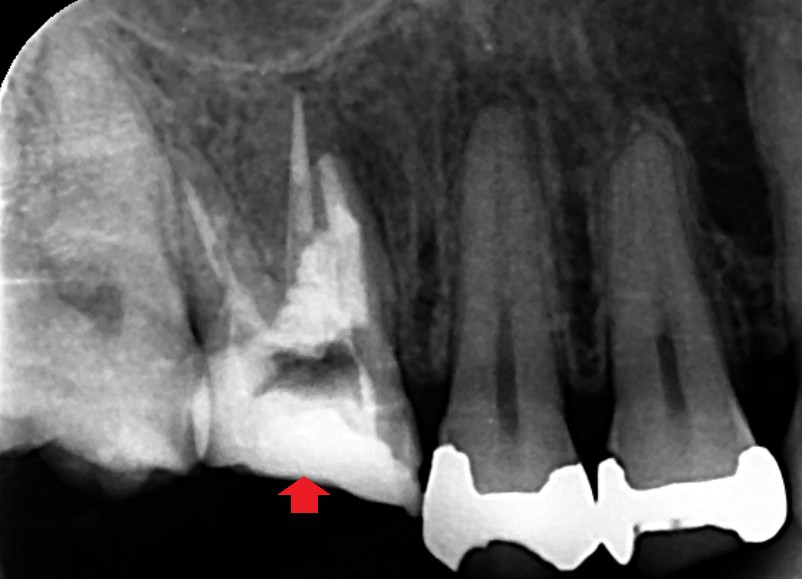

初診時の矢状断のCT画像です。

第一大臼歯のみ精密再根管治療とパーフォレーションリペアを行い、第二小臼歯は根管治療を行わず精密むし歯治療のみをすることにしました。レントゲン画像は、根管充填とパーフォレーションリペア時の画像です。